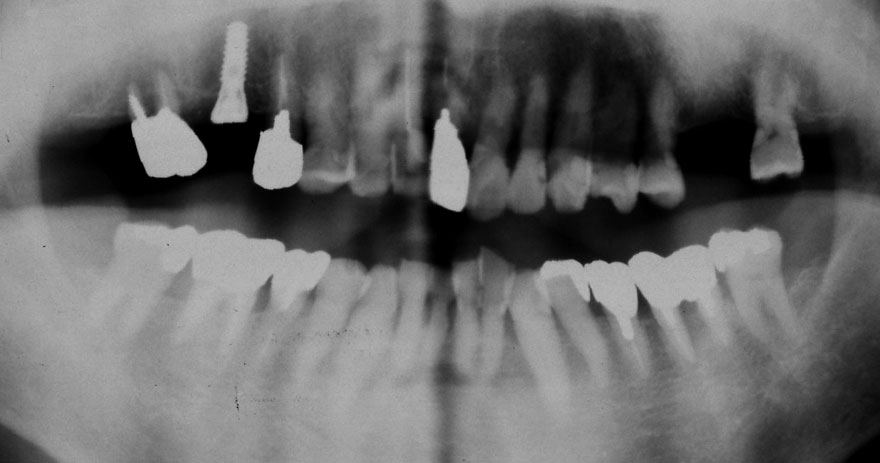

初診時 51歳 男性 平均歯槽骨喪失量:2.83mm

河田歯科医院

21年後 72歳

平均歯槽骨喪失量:2.51mm

21年間再生量:+0.32mm

年間再生速度:+0.015mm

(ケア頻度:1.20ヵ月ごと)